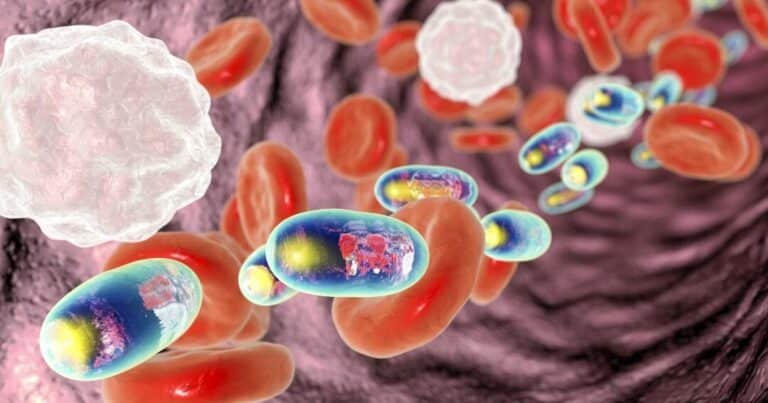

Los avances en nanotecnología han abierto nuevas posibilidades en el campo médico, destacando especialmente los . Estas...

En los últimos años, la investigación farmacéutica ha dado un salto innovador con el desarrollo de medicamentos...